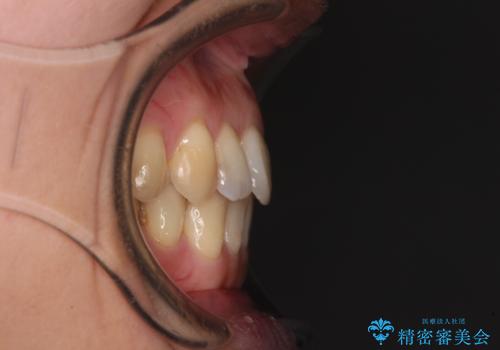

- 上下奥歯の欠損を気にして来院された患者様です。

以前矯正した後戻りにより前歯に叢生が認められたため、矯正治療の提案をしたところ、補綴治療と合わせて矯正治療を行うこととしました。

後戻りの程度は軽度であったため、インビザライン・ライトを用いて歯列を整えました。